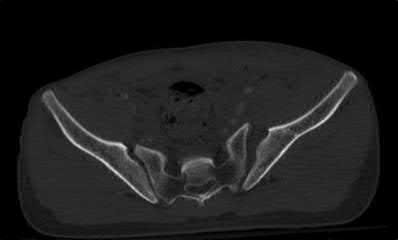

Which of the following images shows an injury pattern most consistent with a lateral compression type 3 pelvic ring injury?

Figure C is an axial CT scan of a lateral compression type 3 (LC3) pelvic ring injury.

Classically, LC3 injuries demonstrate an ipsilateral lateral compression and a contralateral APC (windswept pelvis) fracture pattern. The most common mechanism of injury in these cases is a rollover MVC or pedestrian vs. auto. LC1 injuries are characterized by an oblique or transverse ramus fracture and ipsilateral anterior sacral ala compression fracture, while LC2 injuries consist of a rami fracture and ipsilateral posterior ilium fracture dislocation (crescent fracture). While LC1 injuries can often initially be managed conservatively with protected weight-bearing and close observation, LC2 and LC3 pelvic ring injuries are almost universally operative.

Answer 1: This represents a lateral compression type 2 injury. Answer 2: This represents a lateral compression type 1 injury.

Answer 4: This represents an anterior posterior compression type 2 injury. Answer 5: This represents an anterior posterior compression type 3 injury.